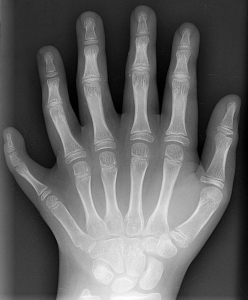

Polydactyly (from Ancient Greek means 'πολύς' (polus) or "many" + 'δάκτυλος' (daktulos) "finger[s]"), also known as polydactylism, sexdactyly, hexadactyly, or hexadactylism, is a congenital physical disorder consisting of supernumerary fingers or toes.

Fully developed and functional extra digits on both hands and feet are considered very rare as a genetic trait in medical history, amid some partial development of an extra digit occurs about twice in every 1,000 white male births. Ordinarily, polydactylism appears as an extra piece of non-functional tissue, typically occurring as an extra finger, sometimes with a bone, but no joint.

"It's merely an interesting and beautiful variation rather than a worrisome thing," said Dr. Michael Treece, a St. Luke's Hospital pediatrician, and the OBGYN who delivered Kamani. He has postaxial polydactyly, which is 10 times more likely to occur in black children, and also more likely to appear in boys.